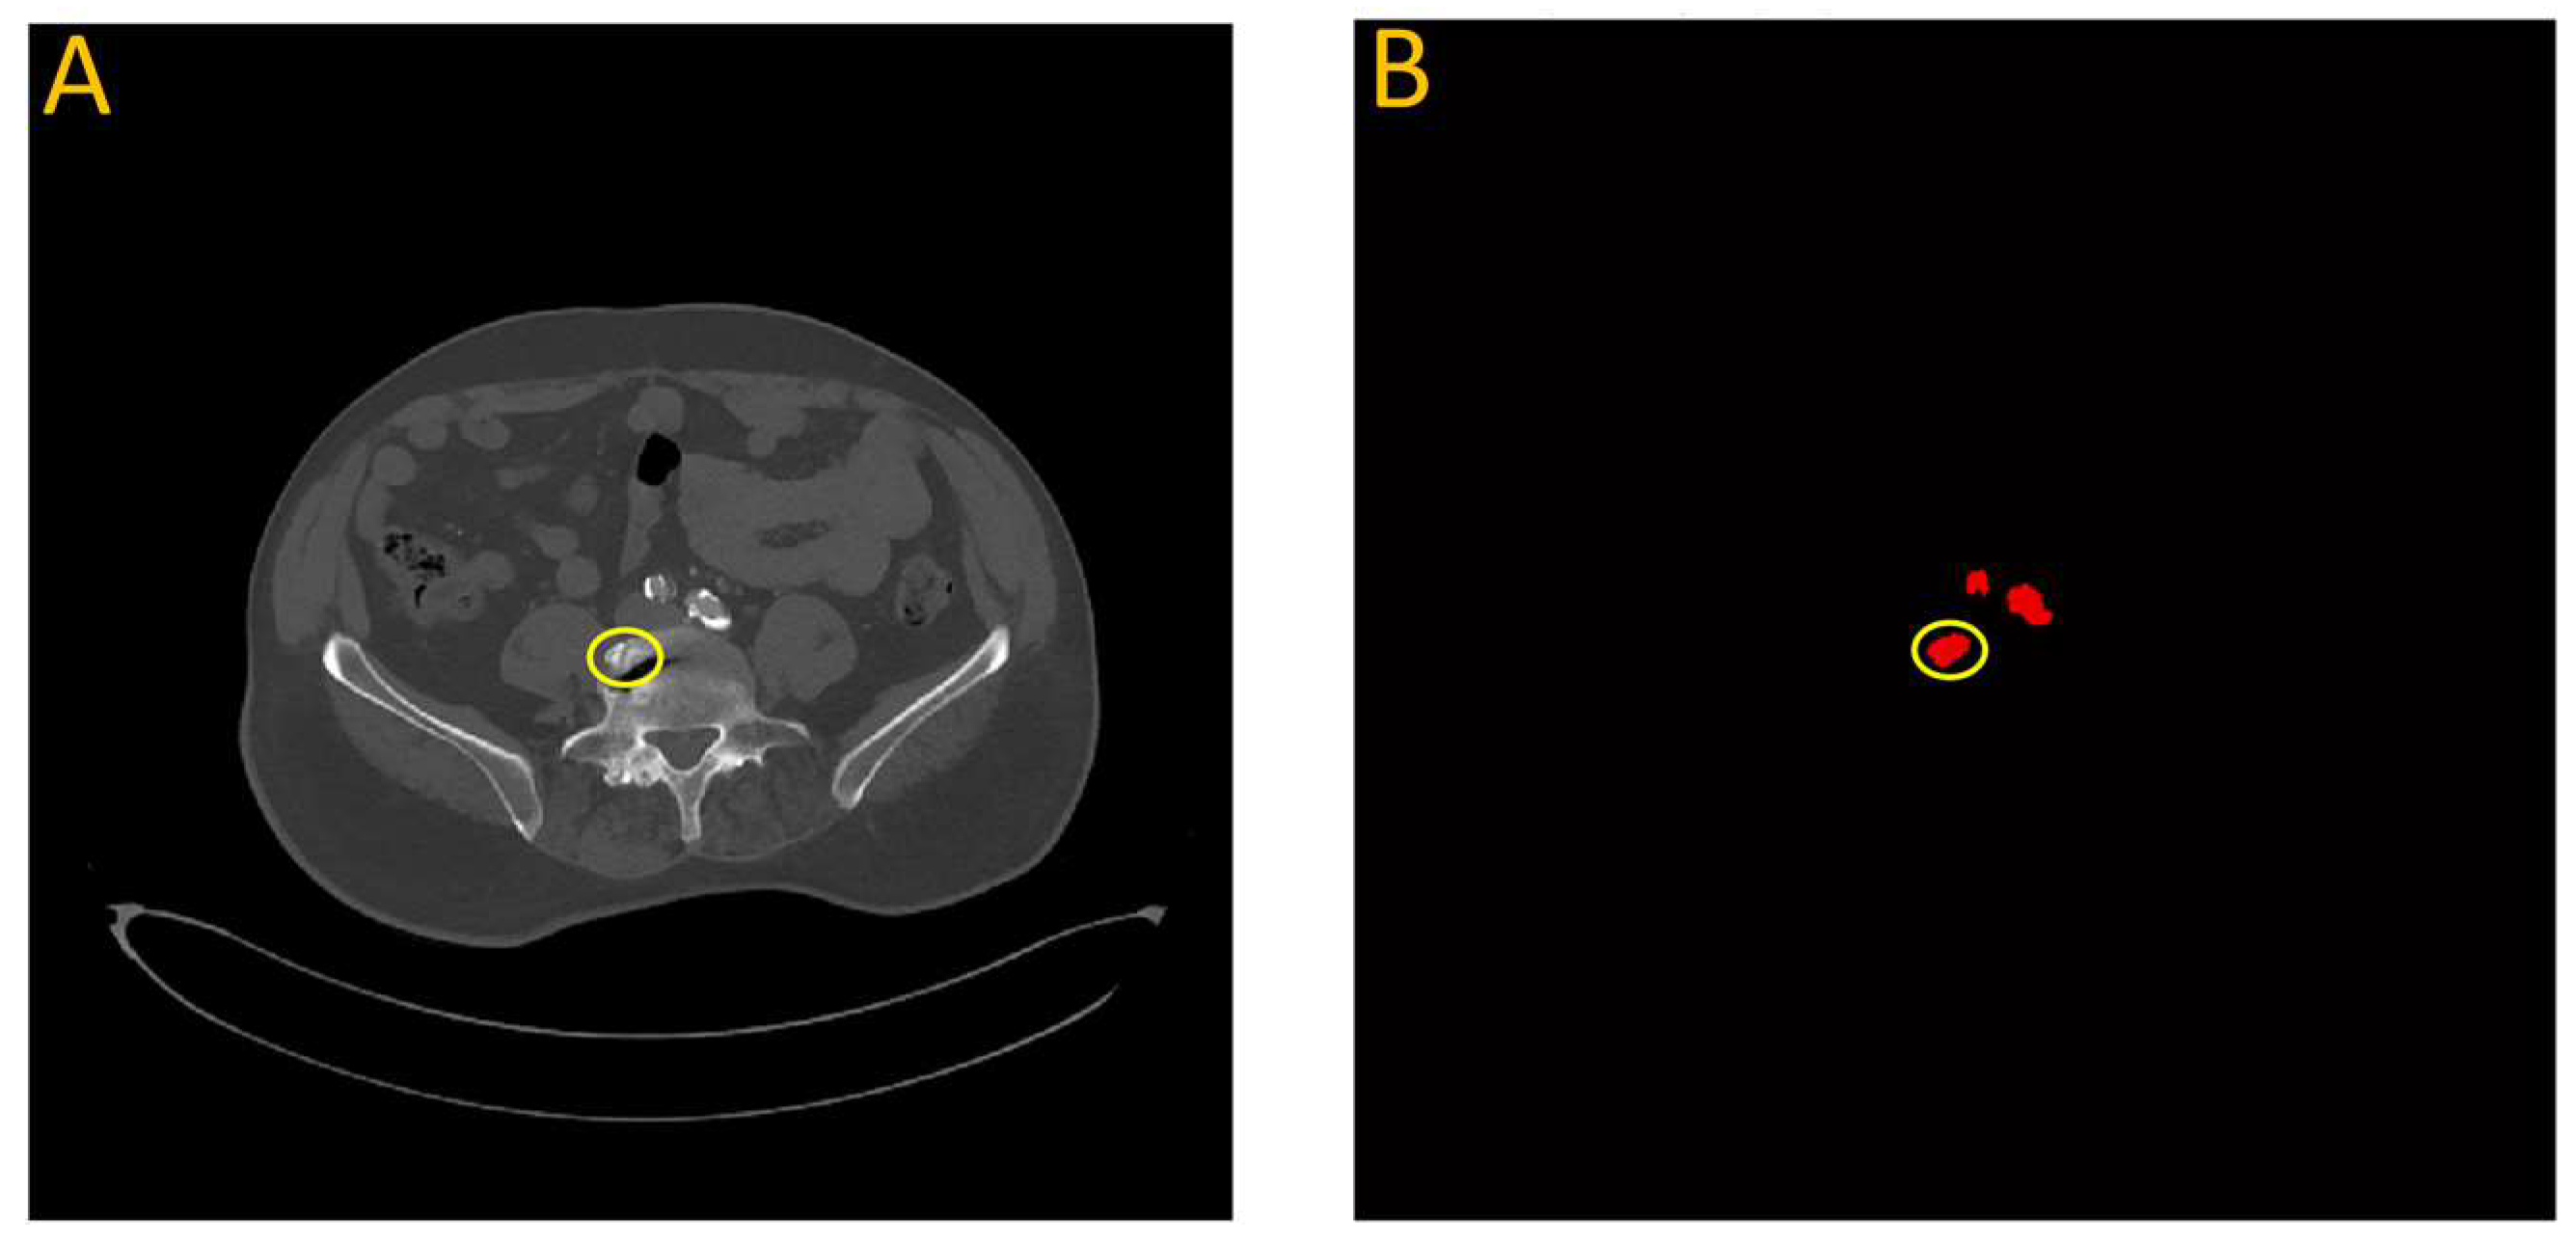

In a few instances where the model overestimated the calcification score, it was often due to a bone structure that bore resemblance to artery features. This is illustrated in Figure 14, which highlights data from testing the first model on patient W25. In this particular case, a section of the vertebra located near the iliac artery displayed similarities to the partially calcified artery itself, just distal to the iliac bifurcation.

Figure 14.

Failure analysis illustrates overestimation in the proposed model. (A) Input image; (B) Automated vascular segmentation using the model. The first model incorrectly identified a section of the vertebra, circled in yellow, as an iliac artery. This misidentification may be attributed to the roughly circular intensity exhibited by this particular vertebral segment, which bears resemblance to the characteristics of the iliac artery.